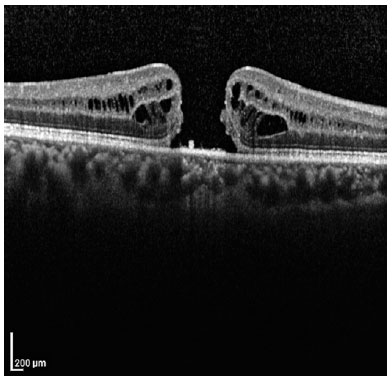

A 68-year-old man who had undergone combined cataract and iFTMH surgery in his right eye (OD) 15 months before at another institution presented at our outpatient clinic for routine examination. The best-corrected visual acuity (BCVA) in OD was counting fingers, with pseudophakia and normal intraocular pressure. Fundus examination evidenced an iFTMH in the right eye; the left eye showed no abnormal findings. The patient’s presurgical spectral domain optical coherence tomography (SD-OCT) study demonstrated a FTMH, but the iFTMH was not measured (Figure 1). A new SD-OCT scan revealed the persistence of the iFTMH, with 326 and 533 microns of mid- and base-hole diameters, respectively (Figure 2A). A new surgery was offered, but the patient declined. Thus, he was set for follow-up every 6 months.

Twenty-one months after his first consultation with us (36 months after the surgery), the BCVA in the right eye had improved to 20/200. Slit-lamp examination revealed posterior capsule opacification while fundus examination and SD-OCT revealed the spontaneous closure of the iFTMH (Figure 2B), with a gap at the foveal ellipsoid zone (EZ).

Twelve months after the verified closure of the iFTMH, posterior capsulotomy was performed, and the BCVA improved to 20/30. At the final visit, 22 months after the closure of the iFTMH, the patient’s BCVA was 20/25, and the gap at the EZ diminished its diameter from 181 microns (Figure 2C) to 94 microns (Figure 2D).